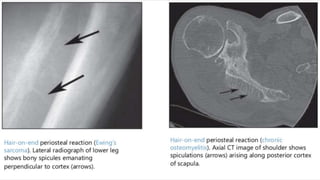

• Periosteal reaction - Codman triangle/Sunburst/Hair-on-end

X-RAY IDENTIFICATION

• Destructive lesion in the diaphysis of a long bone

• “Onion skin” periosteal reaction

(In reality, Ewing sarcoma more often originates in the metaphysis of a long

bone but frequently extends for a considerable distance into the diaphysis)

• Typical “triad’’ of findings on imaging:,

• (1) a “diaphyseal’’ location,

• (2) a “round-cell’’ or “permeative’’ appearance

• (3) an obvious or large soft-tissue mass associated with the tumor

• Periosteal Reaction – Codman’s Triangle, Sunburst Appearance can be seen